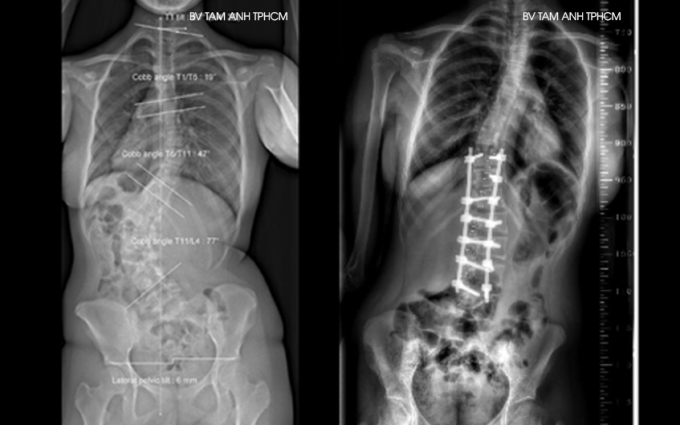

Phim X-quang một người thiếu niên bị cong vẹo cột sống trước (trái) và sau phẫu thuật. Ảnh: Bệnh viện Đa khoa Tâm Anh

Phẫu thuật được chỉ định khi người bệnh không đáp ứng tất cả hướng điều trị nội khoa hoặc bệnh có chuyển biến nặng, cong vẹo cột sống hơn 40 độ. Bác sĩ loại bỏ các thành phần xương, đĩa đệm, dây chằng… bị hư tổn do cột sống cong vẹo gây chèn ép, sau đó nắn chỉnh lại cột sống về gần nhất có thể với đường cong sinh lý tự nhiên và cố định lại bằng móc, vít, thanh nẹp…